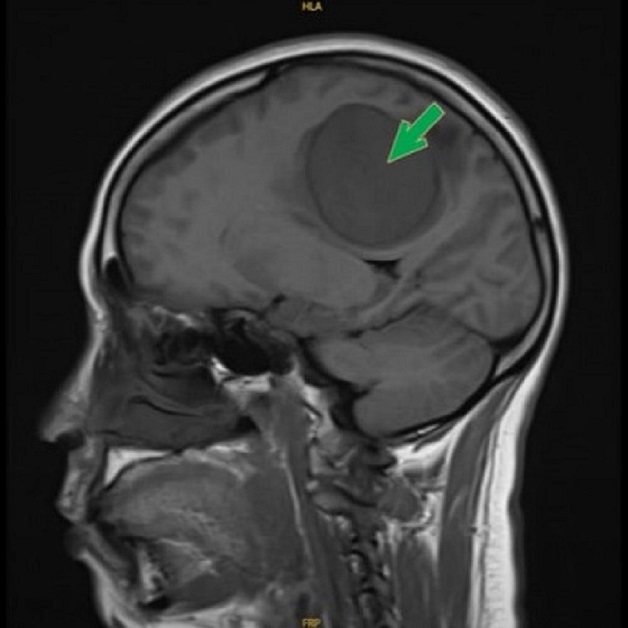

Triệu chứng đau đầu còn thường gặp trong bệnh u não. Cơn đau thường khởi phát từ từ tăng dần, một số tác giả còn mô tả biểu hiện đau đầu này giống như vết dầu loang, đau đầu hay tăng lên về nửa đêm và gần sáng. Ở giai đoạn sớm của bệnh, bệnh nhân có thể chỉ có triệu chứng đau đầu đơn độc, ở giai đoạn muộn hơn sẽ có các dấu hiệu của hội chứng tăng áp lực nội sọ như: buồn nôn, mờ mắt, nhìn đôi; các dấu hiệu thần kinh khu trú tùy thuộc vào vị trí của khối u như: co giật, liệt nửa người, lú lẫn, loạng choạng, ù tai…

U màng não là một trong những nguyên nhân gây đau đầu thứ phát, cần thăm khám sớm và điều trị hiệu quả.